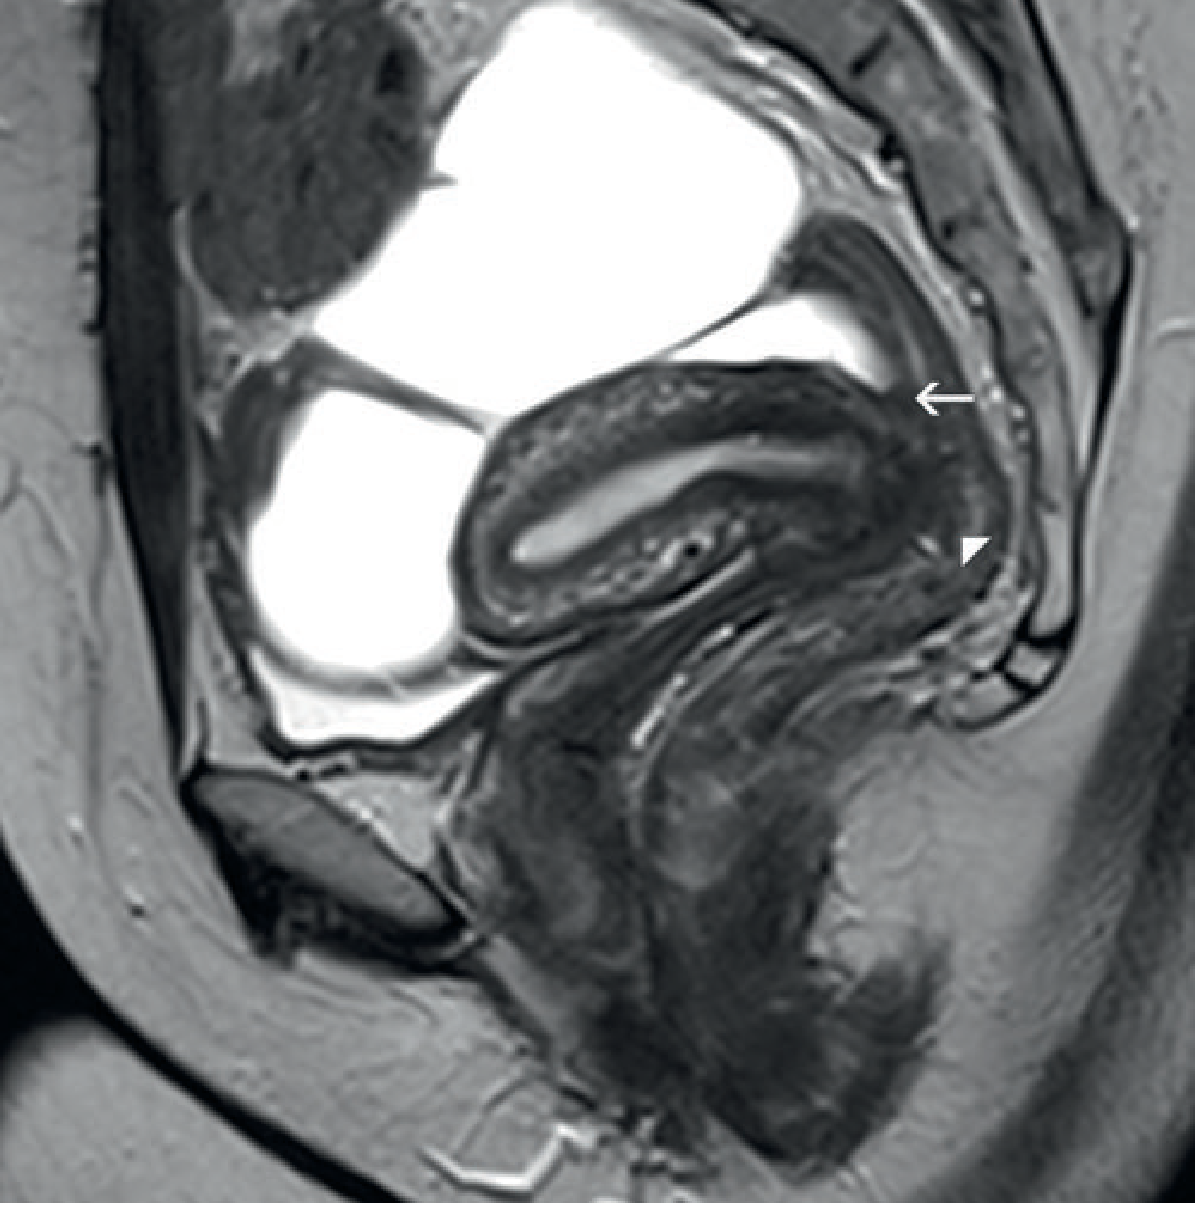

Endometriosis